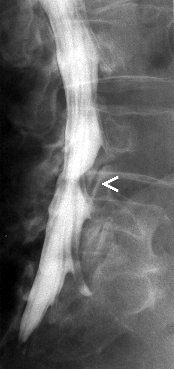

Myelografie is het in beeld brengen

van het ruggenmergkanaal door middel van een cotrasmiddel. Deze wordt

door middel van een punctie ingespoten in de duraal zak in de lage rug.

Er wordt dus in de rug geprikt zodat een naald door kan schuiven tussen

de wervels tot in het ruggenmergkanaal. Dit kan gebeuren onder

plaatselijke verdoving, maar dit is geen regel. Gesteld wordt dat er in

elk geval moet geprikt worden. Er kunnen opnames genomen worden ter

hoogte van de hals, borst of lage rug. Na de punctie worden er

conventionele opnames gemaakt waarna de patiënt naar de CT-scan

wordt gebracht om axiale beelden te maken in de regio waar zich

mogelijk problemen voordoen.

Het is echter zo dat deze onderzoek

steeds vaker vervangen wordt door een MRI vande rug, daar dit minder

invasief is, minder risicos inhoudt en beter verdragen wordt door de

patiënten.